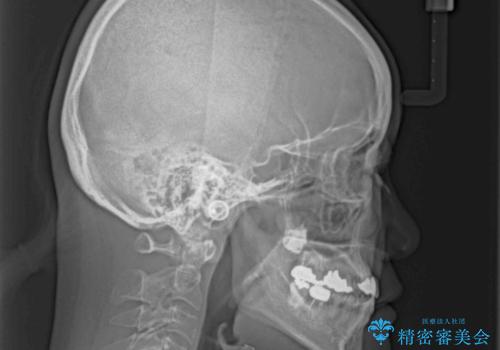

- 前歯の反対咬合により、日々強い痛みを感じているとのことで来院された患者様です。

骨格的に下顎が前方位にありますが、歯列矯正で前歯の被蓋関係を改善することができると判断されたため、インビザラインにより矯正治療を行うこととしました。

また、上顎前歯と下顎大臼歯に神経を取り除いた歯があったため、矯正治療後に、セラミッククラウンにて補綴することとしました。